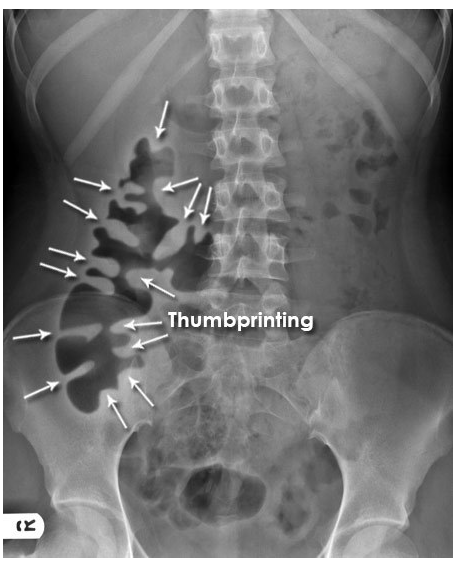

Patient with severe abdominal pain. What does the image show?

What is the likely pathology?

Ascites

Lead pipe colon

Normal gas pattern

Rigler’s/ double wall sign

Thumbprinting

Inflammation of the bowel wall leads to thickening of the haustral folds. This results in the radiological sign of thumbprinting, a characteristic finding in patients with active ulcerative colitis.